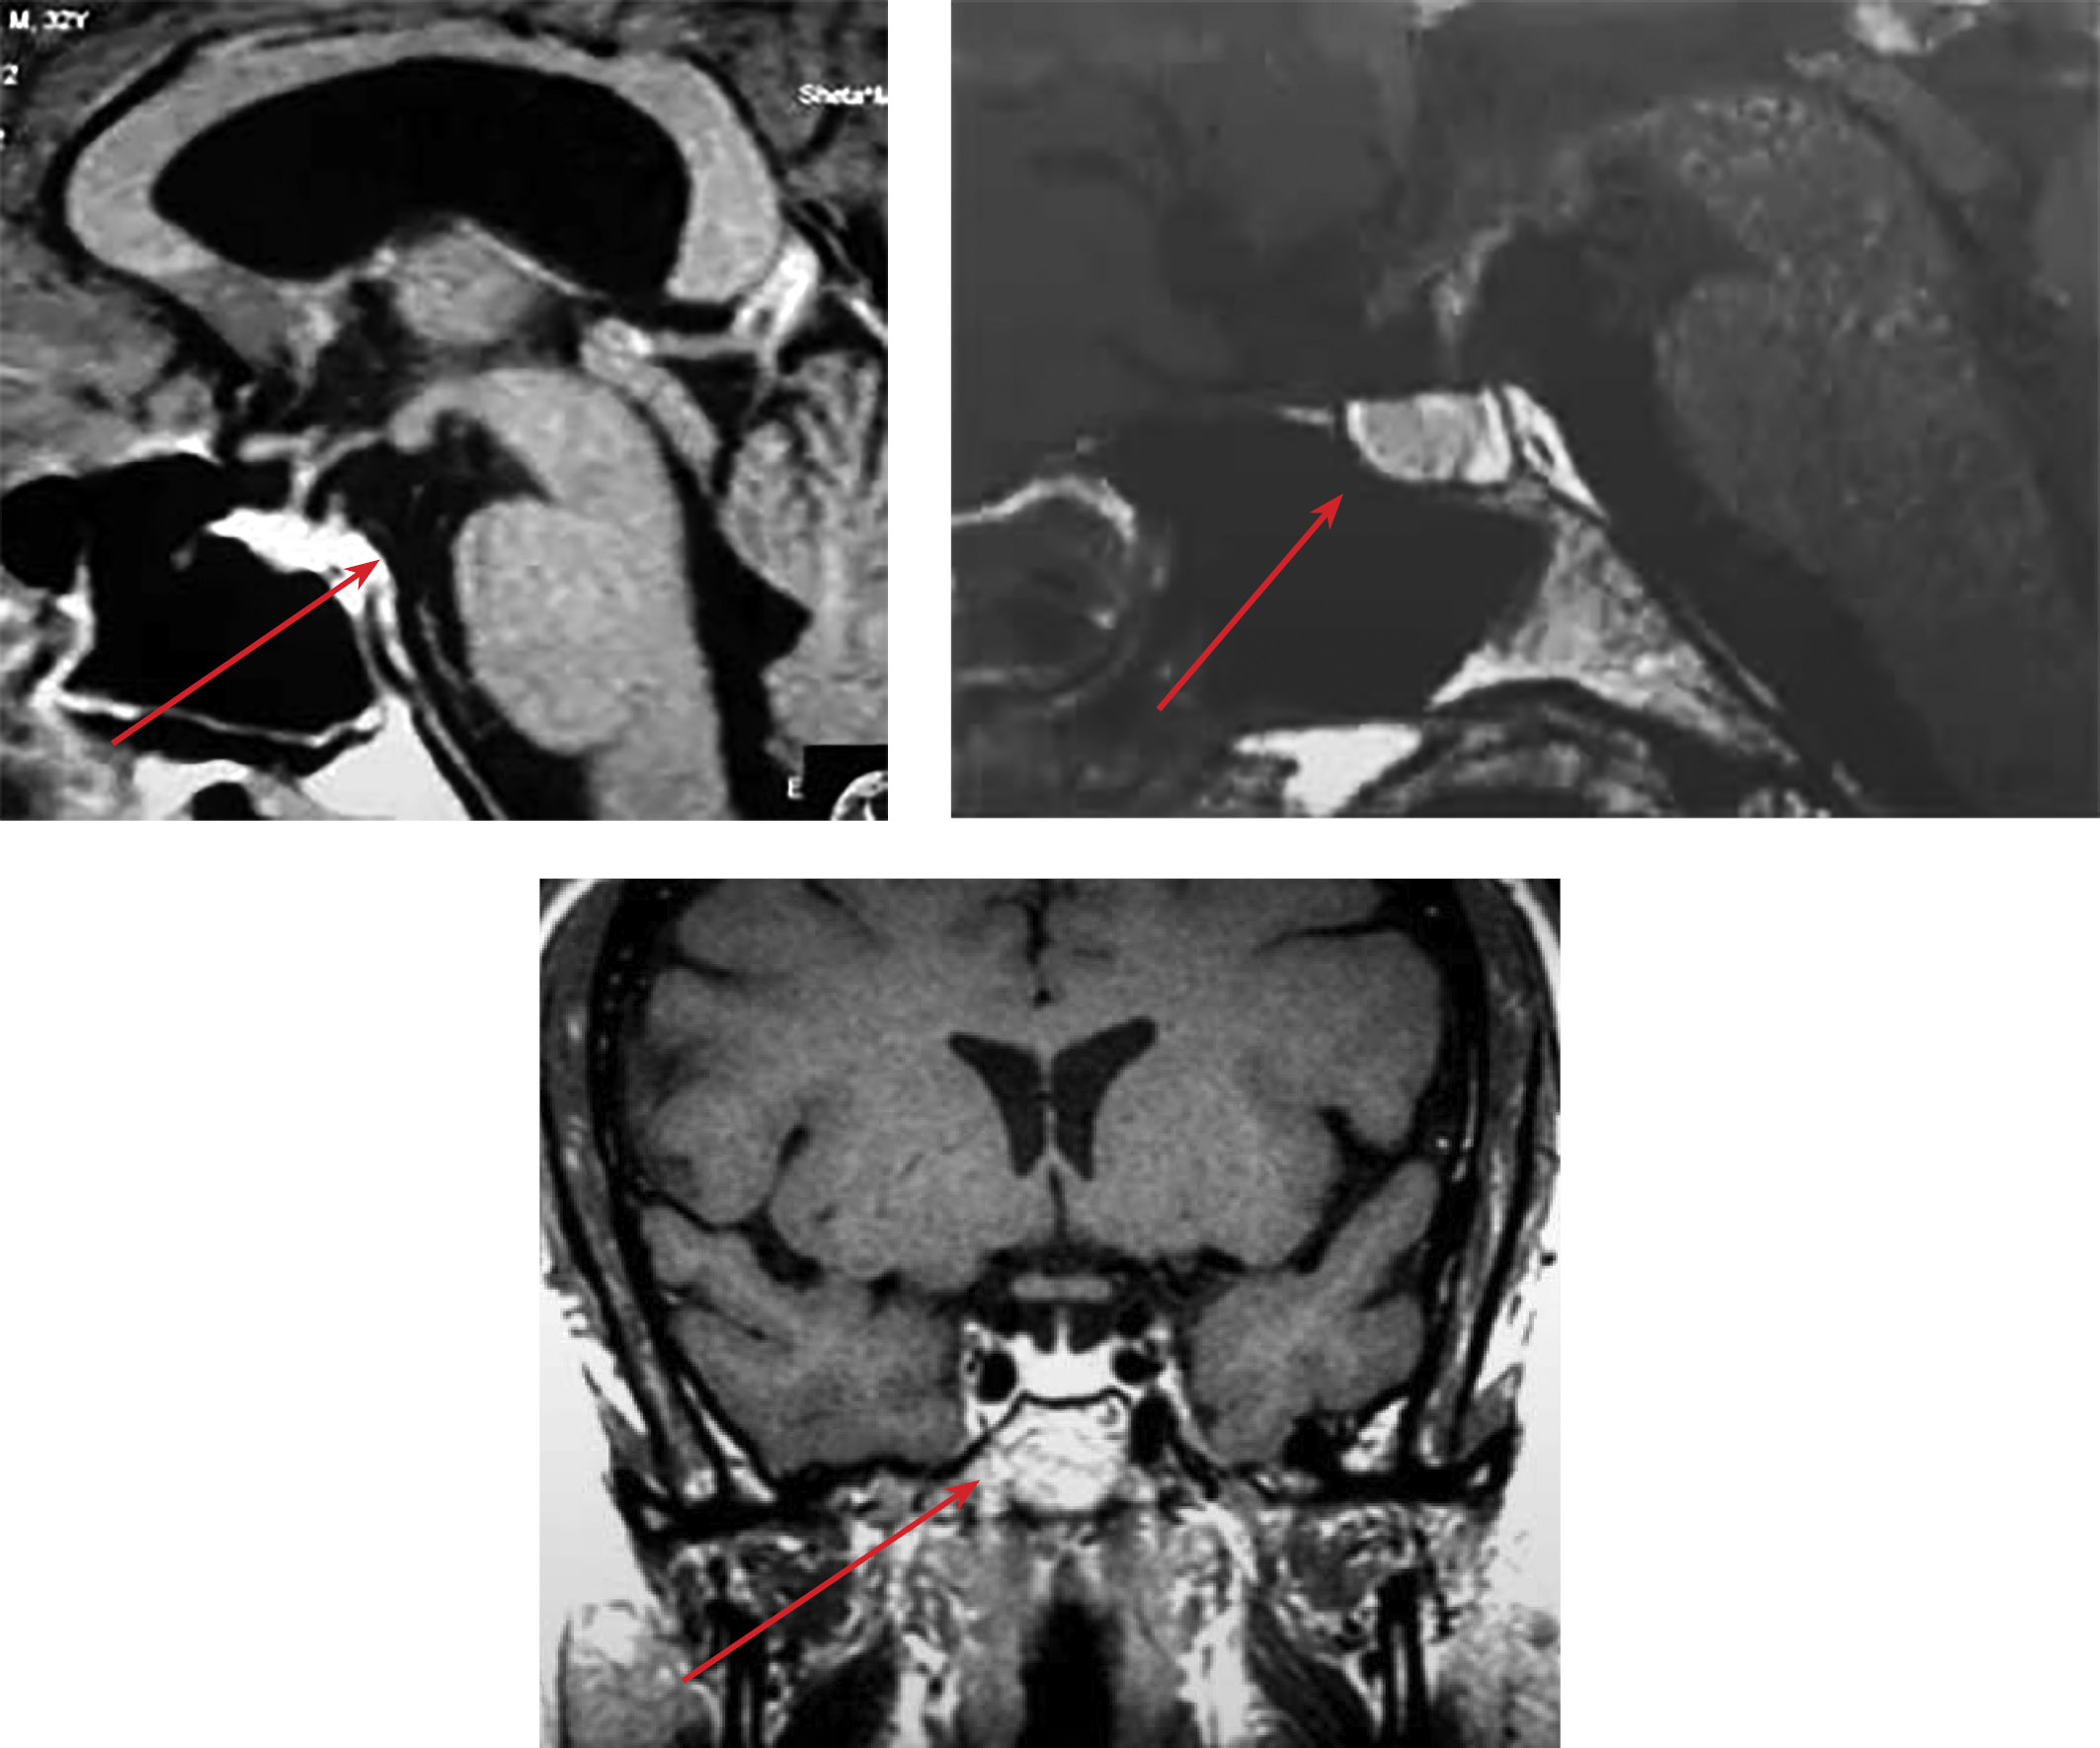

История заболевания. Женщина, 67 лет, поступила в эндокринологическое отделение ГБУЗ ТО «Областная клиническая больница №1» г. Тюмени с жалобами на жажду в дневное время, обильное, учащенное мочеиспускание до 4,5 литра в сутки, снижение аппетита, дисфагию, метеоризм, запор, низкие цифры артериального давления, общую слабость, сухость губ и слизистой рта, кожных покровов, снижение слюноотделения, потерю массы тела на 7 кг в течение текущего года. В ходе сбора анамнеза установлено, что впервые данные жалобы появились 2 года назад, когда пациентка отметила обильное, учащенное мочеиспускание. Амбулаторно консультирована урологом с целью исключения патологии мочевыделительной системы, с учетом полиурии до 5 литров в сутки был заподозрен нефрогенный несахарный диабет. По результатам первичного исследования уролога: в микробиологическом исследовании мочи обнаружена E. coli, в исследовании мочи по Зимницкому колебания удельного веса составляли 1005–1012, показатели водно-электролитного обмена (натрий, калий, хлор) находились в пределах референсного диапазона, показатели белкового обмена — без отклонений, нарушения углеводного обмена не верифицированы. По результату сцинтиграфии почек клинически значимой патологии не выявлено. Далее пациентка консультирована нефрологом ГБУЗ ТО «ОКБ №1» г. Тюмени, который установил диагноз «Хронический тубулоинтерстициальный нефрит, ХБП С2 А1», рекомендован прием дипиридамола (в настоящий момент препарат пациентка не принимает в связи с усилением диспепсических явлений), препараты железа. Неоднократно консультирована эндокринологом амбулаторно, который исключал ЦНД, однако функциональные диагностические пробы не проводились в связи с отсутствием технических возможностей для их проведения на амбулаторном этапе, патологий со стороны надпочечников и щитовидной железы не выявлено. По данным МРТ гипофиза от июля 2021 г., аденомы гипофиза не выявлено, патогномоничного для ЦНД гиперинтенсивного сигнала от задней доли гипофиза на Т1 взвешенных не выявлено (рис. 1). В мае 2022 г. пациентка находилась на стационарном лечении в отделении урологии ГБУЗ ТО «ОКБ №2» г. Тюмени с диагнозом: «Острый восходящий пиелонефрит справа», проведен курс антибактериальной терапии. Анализ мочи по Зимницкому: удельный вес — 1005 г/л, суточный диурез — 3470 мл. Повторно проведена консультация эндокринолога, который также исключил дефицит антидиуретического гормона. Из анамнеза жизни известно, что в настоящее время наблюдается у гастроэнтеролога по поводу хронического постописторхозного холецистита, билиарного сладжа, полипа желчного пузыря, хронического панкреатита, долихосигмы, колоноптоза, тубулярной непролиферирующей аденомы толстой кишки. По рекомендации гастроэнтеролога регулярно получает панкреатин 25 000 ЕД х 3 раза в сутки. Данные за перенесенные нейрохирургические вмешательства, черепно-мозговые травмы пациентка отрицает.

Рисунок 1. МР-данные хиазмально-селлярной области пациента.

Турецкое седло в латеральной проекции (слева)

и cредняя сагиттальная часть гипофиза и турецкого седла (справа),

коронарный срез головного мозга (снизу).

Красными стрелками обозначена локализация селлярной области.

Таким образом, по результатам жалоб (появления жалоб на жажду исключительно в дневное время), данных анамнеза, отсутствия отклонений биохимических и гормональных показателей крови и мочи, результатам МРТ-исследования гипофиза и, наконец, повышения осмоляльности мочи до 653 мОсм/кг на фоне пробы с сухоедением позволило исключить диагноз несахарного диабета и верифицировать первичную полидипсию с большой вероятностью на фоне психогенного компонента. По итогам обследования даны рекомендации по лечению сопутствующих заболеваний у гастроэнтеролога и нефролога, а также с учетом установленного диагноза рекомендована консультация психотерапевта для верификации расстройства питьевого поведения. В настоящее время в заместительной терапии препаратами десмопрессина и проведении МРТ-исследований головного мозга пациентка не нуждается с учетом доказанной нозологии.